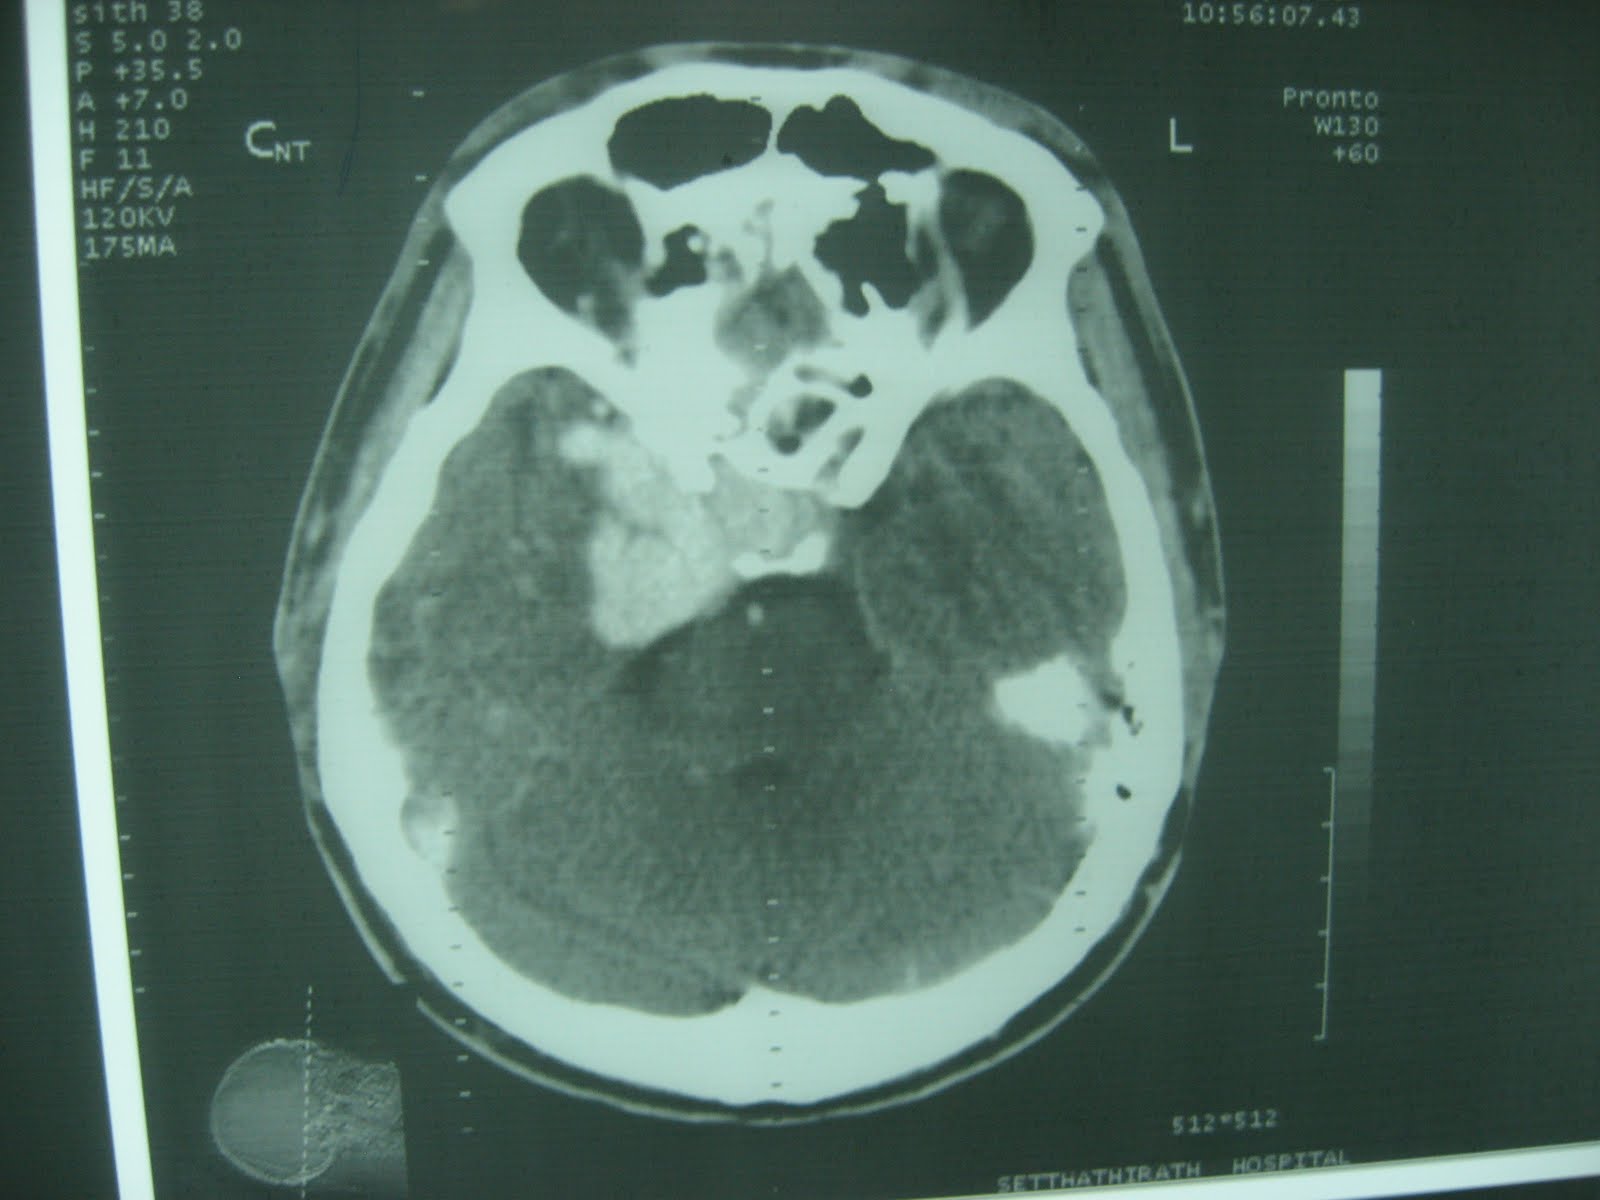

The next day, I was asked to look at his head CT. He had multiple lesions, including an area on the right side that looked like an old stroke or hematoma - mostly empty space where there should have been brain - an 2 spots that light up homogeneously with contrast - one near the left ear, and one on the right, at the very front of the brain near the pituitary gland and optic nerves. And it looked like maybe he had an old fracture in his right sinuses that had not completely healed. The enhancing lesions looked most like tumor - they were very regular - but I was praying for infection (or something else we could treat.) Either way, it was clear he needed an MRI and a neurologist, so the residents sent him home with plans to see Lao’s only neurologist (and a HF internal medicine residency grad) after his MRI in Thailand. A week and a half or so later, he returned to Setta with his MRI read. 11 pages of images in a 5x6 grid. The residents asked me to interpret it for them, because there was no read.